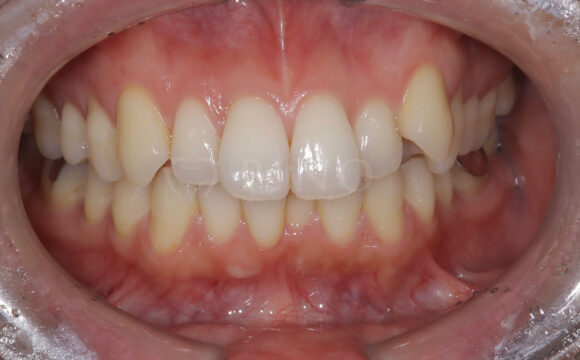

症例12:噛み合わせが深く、下の歯が見えないのが気になる(20代男性)

主訴 噛み合わせが深く、下の歯が見えないのが気になる 診断名 過蓋咬合(かがいこうごう)、顎関節後方転位 治療方法 マウスピース矯正、補綴治療(被せ物、詰め物の治療) 抜歯 なし オルソパルス あり 治療期間 2年 費用 746,000円 + 165,000円(オルソパルス)+ 補綴費用(保険診療) 副作用・注意点 矯正後の後戻りを防ぐためリテーナーの使用が必要となる、詰め物の変色が起こる可能性がある 備考 下顎の位置を正しい位置にするためにスプリントを使用した。ホワイトニングも併用。